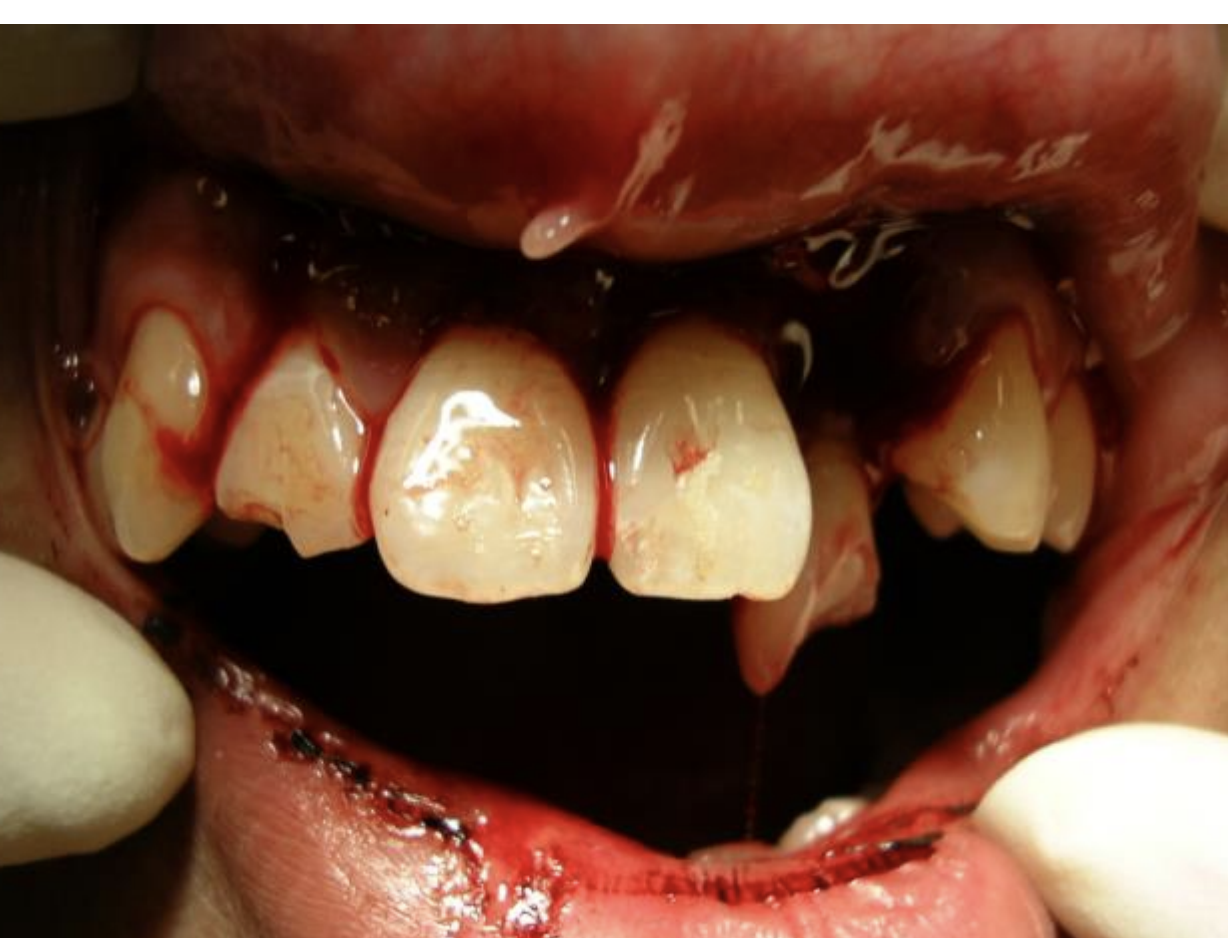

20

Q

delay to dentist - describe ED management

A

• Ideally need OPG to assess fracture of alveolar bone

• Local anaesthetic analgesia

• Reinsert tooth into normal position

• Splint to adjacent teeth with Glass Ionomer Cement (GIC). If no GIC available need

alternate splint – e.g. “blue tac” and a mouth guard

• Cover exposed fracture surface (dentine) with GIC

• If no GIC available needs relatively urgent (< 24h) f/u with dentist

• Will need splinting for 2-4 weeks

• adt

• abx

How well did you know this?